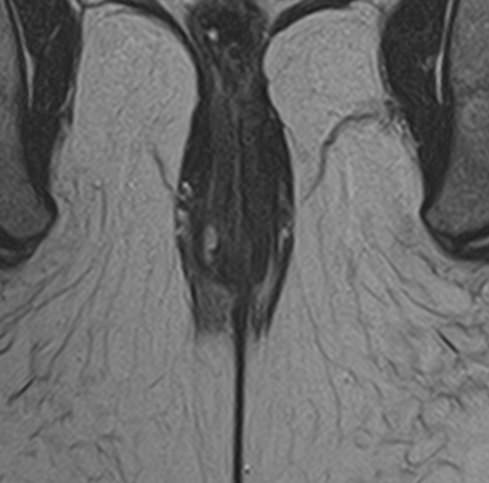

МРТ аноректальной области с контрастным усилением – это специализированное исследование, используемое для детального изучения структур и патологий в области ануса, прямой кишки и окружающих тканей. Контрастное усиление помогает улучшить видимость кровеносных сосудов и определить границы патологических образований.

• Фистулы и свищи: Определение хода и точного расположения аноректальных свищей.

Преимущества МРТ аноректальной области включают высокую детализацию мягких тканей и отсутствие ионизирующего излучения. Контрастное усиление помогает лучше визуализировать сосуды и патологические изменения.

В целом, МРТ с контрастным усилением является безопасной и информативной процедурой для диагностики различных заболеваний аноректальной области.